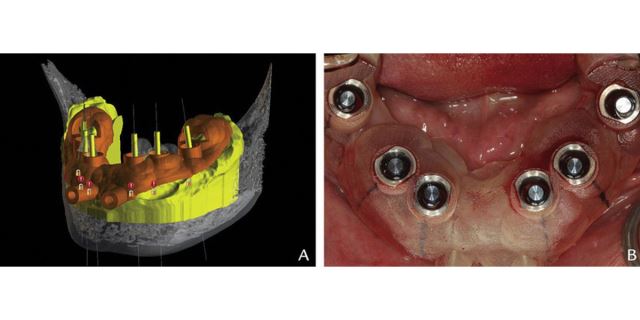

مرحله چهارم

در این مرحله به کمک CAD-CAM یک گاید به صورت قالب پلاستیکی ساخته می شود. این مرحله برای قرار دادن ایمپلنت نهایی بسیار کمک دهنده می باشد. گاید تهیه شده در دهان بیمار قرار داده می شود تا بدون برش ایمپلنت درون جایگاه مورد نظر قرار بگیرد.

مرحله پنجم

در مرحله آخر و در روز جراحی و بلافاصله بعد از قرار دادن ایمپلنت، روکش ایمپلنت که دارای ظاهری بسیار طبیعی و زیبا می باشد، برای بیمار نصب خواهد شد. در واقع در روش ایمپلنت دیجیتال، بیمار حتی یک روز هم بدون دندان نمی ماند.